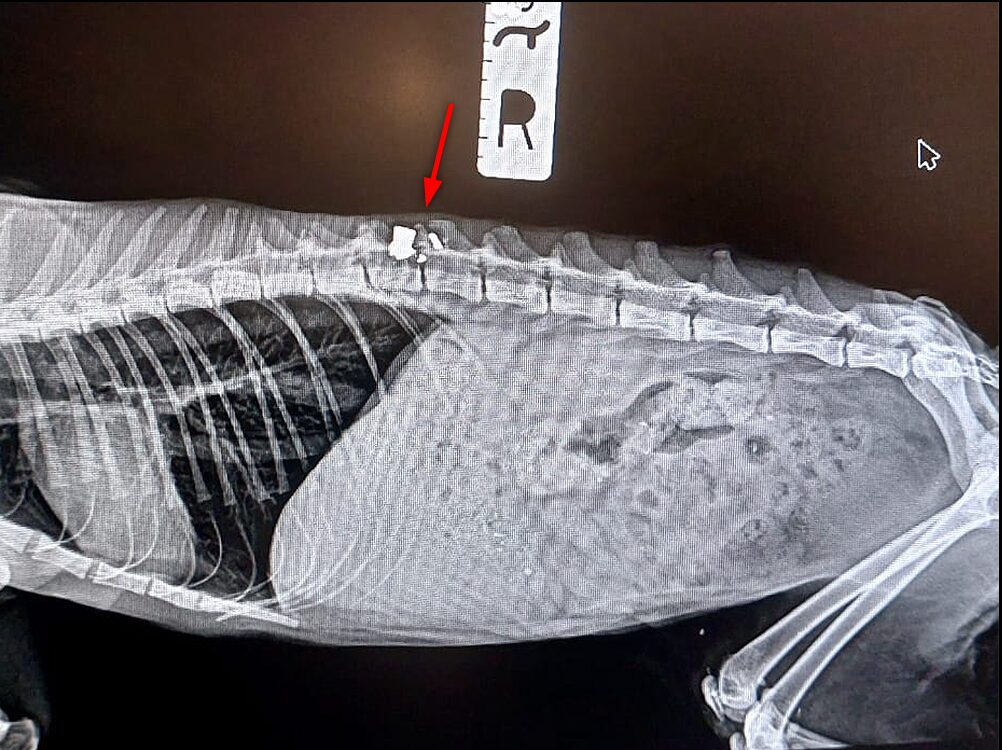

We rushed her to The Vets Jávea, where Norbert, the duty veterinary, immediately sprang into action. What the X-rays revealed was nothing short of devastating. A pellet from an airgun was embedded deep in her back. Shattered fragments surrounded her spinal nerves, likely causing unimaginable pain. The wound wasn’t fresh as scar tissue had formed, evidence that she had been silently suffering for days or longer.